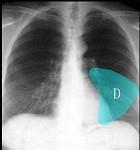

如图所示正常胸部X线影像图像上,该英文字母所代表的肺段为 ( )A.尖段B.后段C.尖后段D.舌叶上段E.舌叶下段

问题 如图所示正常胸部X线影像图像上,该英文字母所代表的肺段为 ( )

选项 A.尖段 B.后段 C.尖后段 D.舌叶上段 E.舌叶下段

答案 E